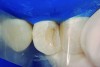

The partial pulpotomy was performed for tooth No. 7 due to the pulp exposure during the caries removal procedures (Figure 5). The superficial contaminated pulp tissue was removed with a No. 1012 spherical diamond bur at high speed with water cooling to allow a better reparative response. This procedure was limited to removal of the infected dentin and damaged pulp tissue, removing the injured odontoblast cell layer. During this step, the remaining pulp tissue was analyzed and found to have good consistency and abundant red bleeding (Figure 6). After the pulpotomy, a solution of calcium hydroxide was used for irrigation along with a sterile cotton pellet to achieve hemostasis and disinfection. After hemostasis, the tooth was treated with direct pulp capping: the exposed area was covered with calcium hydroxide powder (Figure 7) and calcium hydroxide cement (Figure 8). The cavity was provisionally restored with the use of a restorative GIC (Figure 9).

Fig 7. Exposed pulp tissue covered by calcium hydroxide powder.

Figure 7

Fig 8. Calcium hydroxide powder covered by calcium hydroxide cement.

Figure 8

Fig 9. Provisional restoration with GIC.

Figure 9